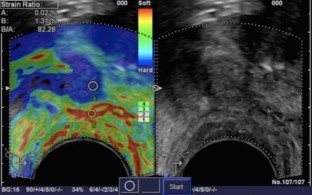

New ultrasound technologies, including color- and power Doppler ultrasound, contrast enhanced US and real-time sonoelastography have shown to improve prostate cancer diagnosis.

Contrast-enhanced ultrasound has shown a sensitivity of 100% (95% CI, 95%), a negative predictive value (NPV) of 99.8% and a positive predictive value (PPV) of 88.8% for prostate cancer detection. Real-time sonoelastography has shown a sensitivity of 86%, a specificity of 81% and NPV of 91% for prostate cancer diagnosis.

Most studies show that these new ultrasound modalities demonstrate a 1.5 to 2.5 times higher detection of prostate cancer per biopsy specimen compared with systematic biopsy. Multicenter studies results are at present lacking but are, however ongoing.

In patients with suspected prostate cancer (elevated PSA, suspicious DRE) these new ultrasound techniques should be used. These techniques can detect prostate cancer and allow a targeted biopsy approach.

• Sonoelastographie

• Elastography